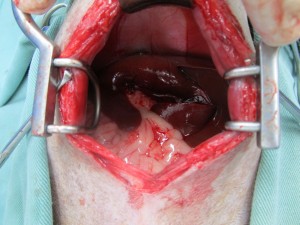

肝臓の間にはまっている胆嚢を丁寧に剥離し、2重結紮し切離しました。

摘出した胆嚢組織は内部がゼリー状に変性を起こしており、胆汁が正常に消化管へ流れていないことが予想されました。